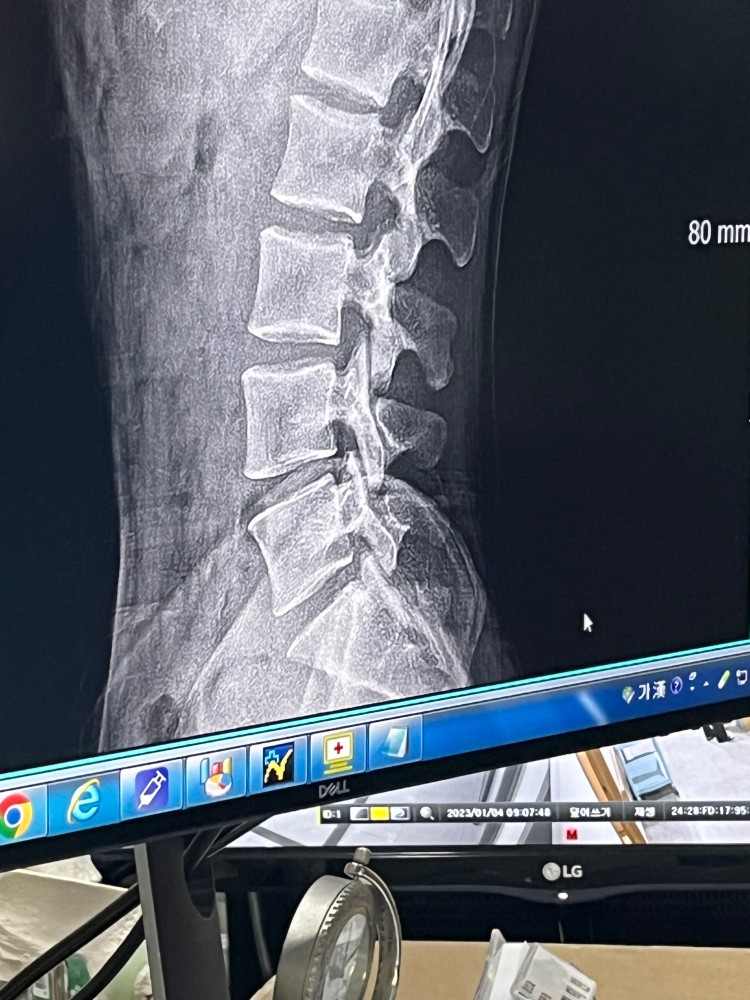

허리 디스크 이정도면 심한가요?

스쿼트 하다가 잘 못 해서 허리가 아파 병원에 갔습니다

엑스레이 사진인데 디스크 심한 편인가요?

통증은 많이느끼는데 수술해야할지 고민이네요

엑스레이로 디스크의 정도를 감별하기는 어렵지만 주어진 사진만으로 봤을때는 심각한 정도는 아닐것 같습니다.

• 유감스럽지만 엑스레이 검사를 통해서 디스크를 관찰할 수는 없습니다. 간접적으로 척추 사이의 간격이 좁아진 것을 통해서 어느 정도 추론해볼 수는 있지만, 올리신 사진 속의 척추 간격에는 특이 사항이 없습니다. MRI 검사를 통해서 정밀하게 상태 평가를 해보아야 디스크의 정도 및 수술 필요성에 대한 평가가 가능할 것입니다.

엑스레이 사진으로는 허리 디스크를 평가할수가 없습니다.

MRI 촬영이 디스크 확인에 도움이 됩니다.